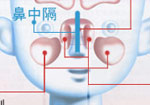

鼻中隔彎曲症(びちゅうかくわんきょくしょう)

鼻を左右に分けている仕切りが強く曲がっている状態です。

鼻出血や鼻づまりの原因になります。